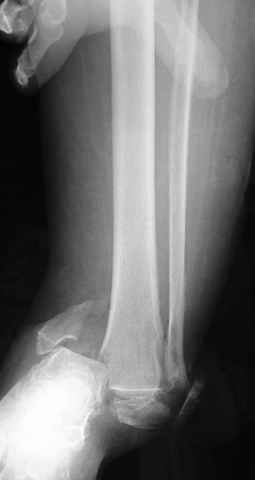

Традиционная техники АО, открытая, с точной репозицией суставной поверхности и жесткой фиксацией, из-за серёзных осложнений, которые

заканчивались ампутацией, уходит в прошлое.

Техника сегодня более щадящая, временные несложные аппараты наружной фиксации: Spanning 2 pin ExFix, Traveling traction для лигаментотаксиса, иначе сокращенные мягкие ткани невозможно восстановить позже.

За последнее 10-12 лет после стабилизации малоберцовой кости, стали применять более усовершенный, сложный, хорошо вам известный метод

Илизарова (кстати наряду с тибиал плато, пилон является одним из показанием по применению аппарата Илизарова при травмах) или Hybrid

Fixator, из минимальных доступов комбинированный метод для восстановления суставной поверхности-фиксация каннулированными

шурупами, создания жесткой системы фиксации до сращения перелома, защита от вальгусной деформации и на место образовавщегося метафизарного дефекта- костная пластика ауто костью или его

синтетические заменители, это сегодняшная тактика лечения.

Дистракция в аппарате или на вытяжение результат - лигаментотаксис, посмотреть бы, как сегодня расположены отломки.